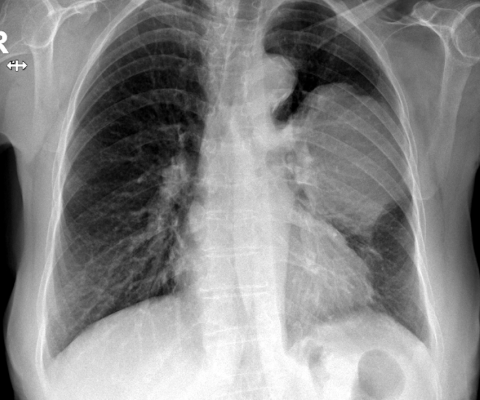

Рентгеновские снимки тератомы средостения: Диагностика и лечение

Раздел: Фотоэссе